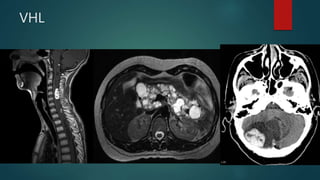

VHL

HIPPEL

• H: haemangioblastoma

• I: increased risk of renal cell cancer

• P: phaeochromocytoma

• P: pancreatic lesions (cyst, cystadenoma, cystadenocarcinoma)

• E: eye dysfunction (retinal haemangioblastoma), endolymphatic sac

tumours

• L: liver, renal and pancreatic cysts